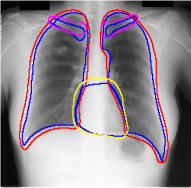

Table 1 shows the segmentation results of different methods with synthetic noisy label settings on JSRT , ISIC 2017 and Brats 2020 dataset. Note that QAM cannot be applied to Brats 2020 dataset because their network is designed for 2D only. We compare DICE score (DSC) on testing sets (against the clean labels). For each setting, we train 5 different models, and report the mean DSC and standard deviation. In and , where biases show up in noisy labels, the proposed method outperforms the baselines by a big leap in total case. The compared methods, however, only work when little bias is included, like . is equivalent to setting in our Markov model, resulting in . We also test the proposed method on real-world label noise, results shows in Table 2. Figure 5 shows examples of label correction results. We provide more qualitative results in the Appendix A.4.

A.4 Qualitative Results

We provide qualitative results for prediction on test images in Fig. A.6 and Fig. A.7 as two sub parts. We also show the label correction on training images in Fig. A.5.